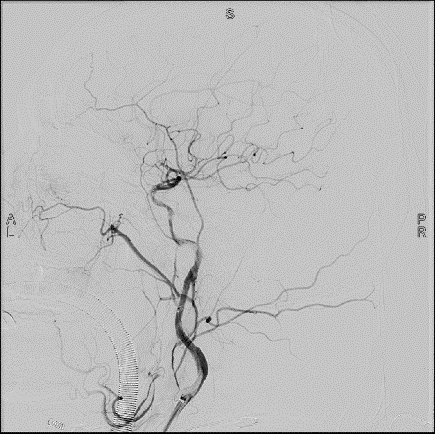

由于患者的左側大腦半球的血液代償體系建立不好,處于嚴重低灌注狀態,導致腦供血不足,存在較高的腦梗死復發風險,且患者逐步出現認知功能減退的現象。面對這種情況,第十一批上海援疆專家、喀什二院神經內科主任王子高帶領團隊精心制定手術方案,決定實施左側頸內動脈閉塞開通術。長節段頸內動脈閉塞開通術手術難度大,對術者要求極高,不僅需要具有嫻熟的微導絲、微導管操控技能,更需要有堅持不懈的耐心和應對各種并發癥,處變不驚的能力。在完善相關檢查及充分術前準備后,王子高帶領神經內科介入團隊在全麻下為該患者實施了左側頸內動脈閉塞開通術,歷時3個小時,該患者左側頸內動脈實現完全再通,術后狀態良好,患者阿先生說:“我現在頭也不昏了,眼睛看東西也更亮了!”

王子高主任表示:“腦動脈非急性閉塞開通術是缺血性腦血管介入治療中難度系數最高的手術,且閉塞節段越長,手術風險越高。該患者的頸動脈閉塞便屬于這種‘最難啃的硬骨頭’,但卻又是不得不去啃的‘硬骨頭’?!?/p>